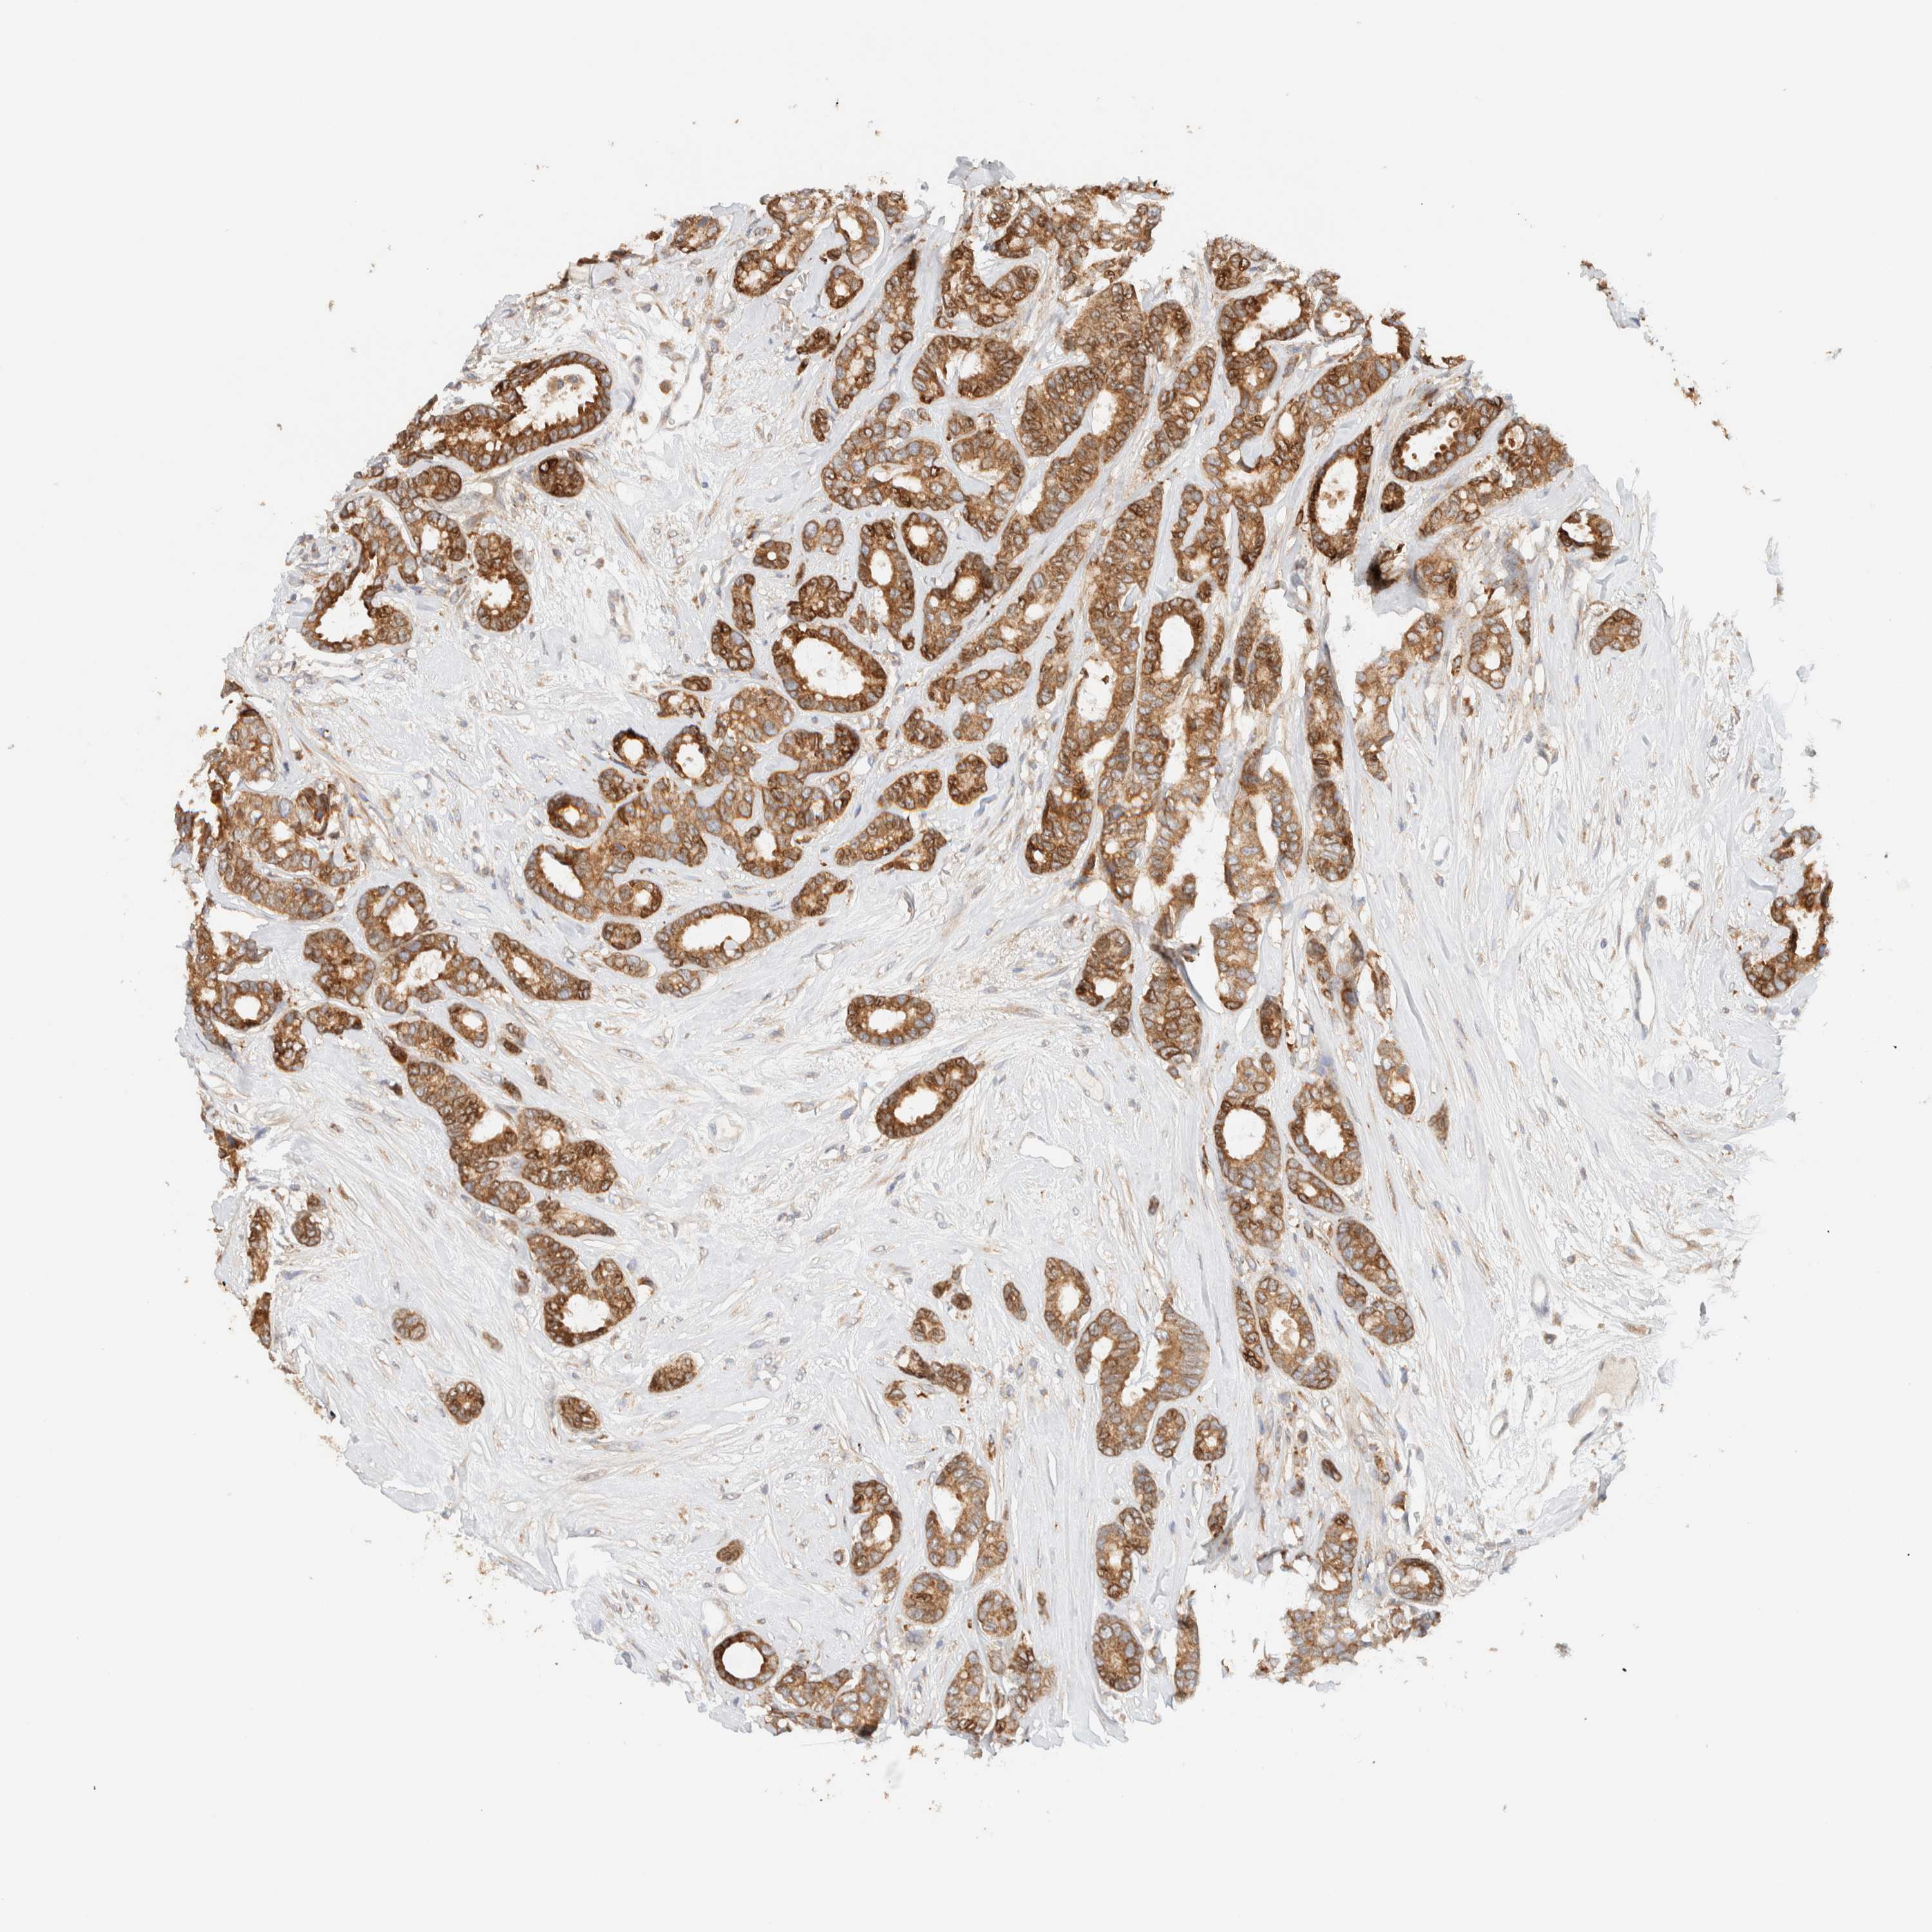

CANCER BREAST CANCER Show tissue menu

BRCA TCGA BRCA VALIDATION PROTEIN EXPRESSION

Breast cancer

Human cancer